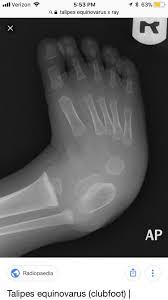

Both the tibia and fibula may be in the same image as the medially deviated foot and the foot may additionally appear plantar flexed. The affected feet or foot may also have a crease along the sole. The foot may be smaller than a normal foot by up to a half-inch.

Babies suffering from the condition which is also called talipes equinovarus or TEV will appear to have deformed feet that dramatically curl inward. Without treatment the foot remains deformed and people walk on the sides of their feet. Casting for Club Foot.

The affected foot and leg may be smaller in size compared to the other. Child feet injury club feet baby birth defects use shoes club foot treatment children feet deformation woman foot treadmill clubfoot feet fitness intensive care. Club foot medically known as talipes equinovarus is a congenital condition affecting the foot.

One should not delay in giving treatment to the child born with club foot and it is good to start the therapy before the baby learns to walk. Children born with club foot have drawn up heels downward pointed toes and feet with high arches. The foot has a typical appearance of pointing downwards and twisted inwards.

Club foot can develop in mature horses too for similar reasons---any injury or chronic pain that causes a horse to consistently favor one foot can lead to contracting and shortening of the muscles and tendons specifically the deep digital flexor tendon and muscle apparatus in that leg eventually pulling the foot into a more upright position. Clubfoot otherwise known as talipes equinovarus is a deformity affecting the foot and the ankle wherein it is turned inward and downward. Club foot - club foot stock illustrations sister helping disabled baby brother - club foot stock pictures royalty-free photos images Muzahidul is 25 months old and being treated for Club Foot.

Clubfoot is a birth defect where one or both feet are rotated inward and downward. Where only one foot is affected the clubfoot is likely to be smaller and broader than the normal foot. The tendons in the babys leg and foot are shorter and tighter than they should be.